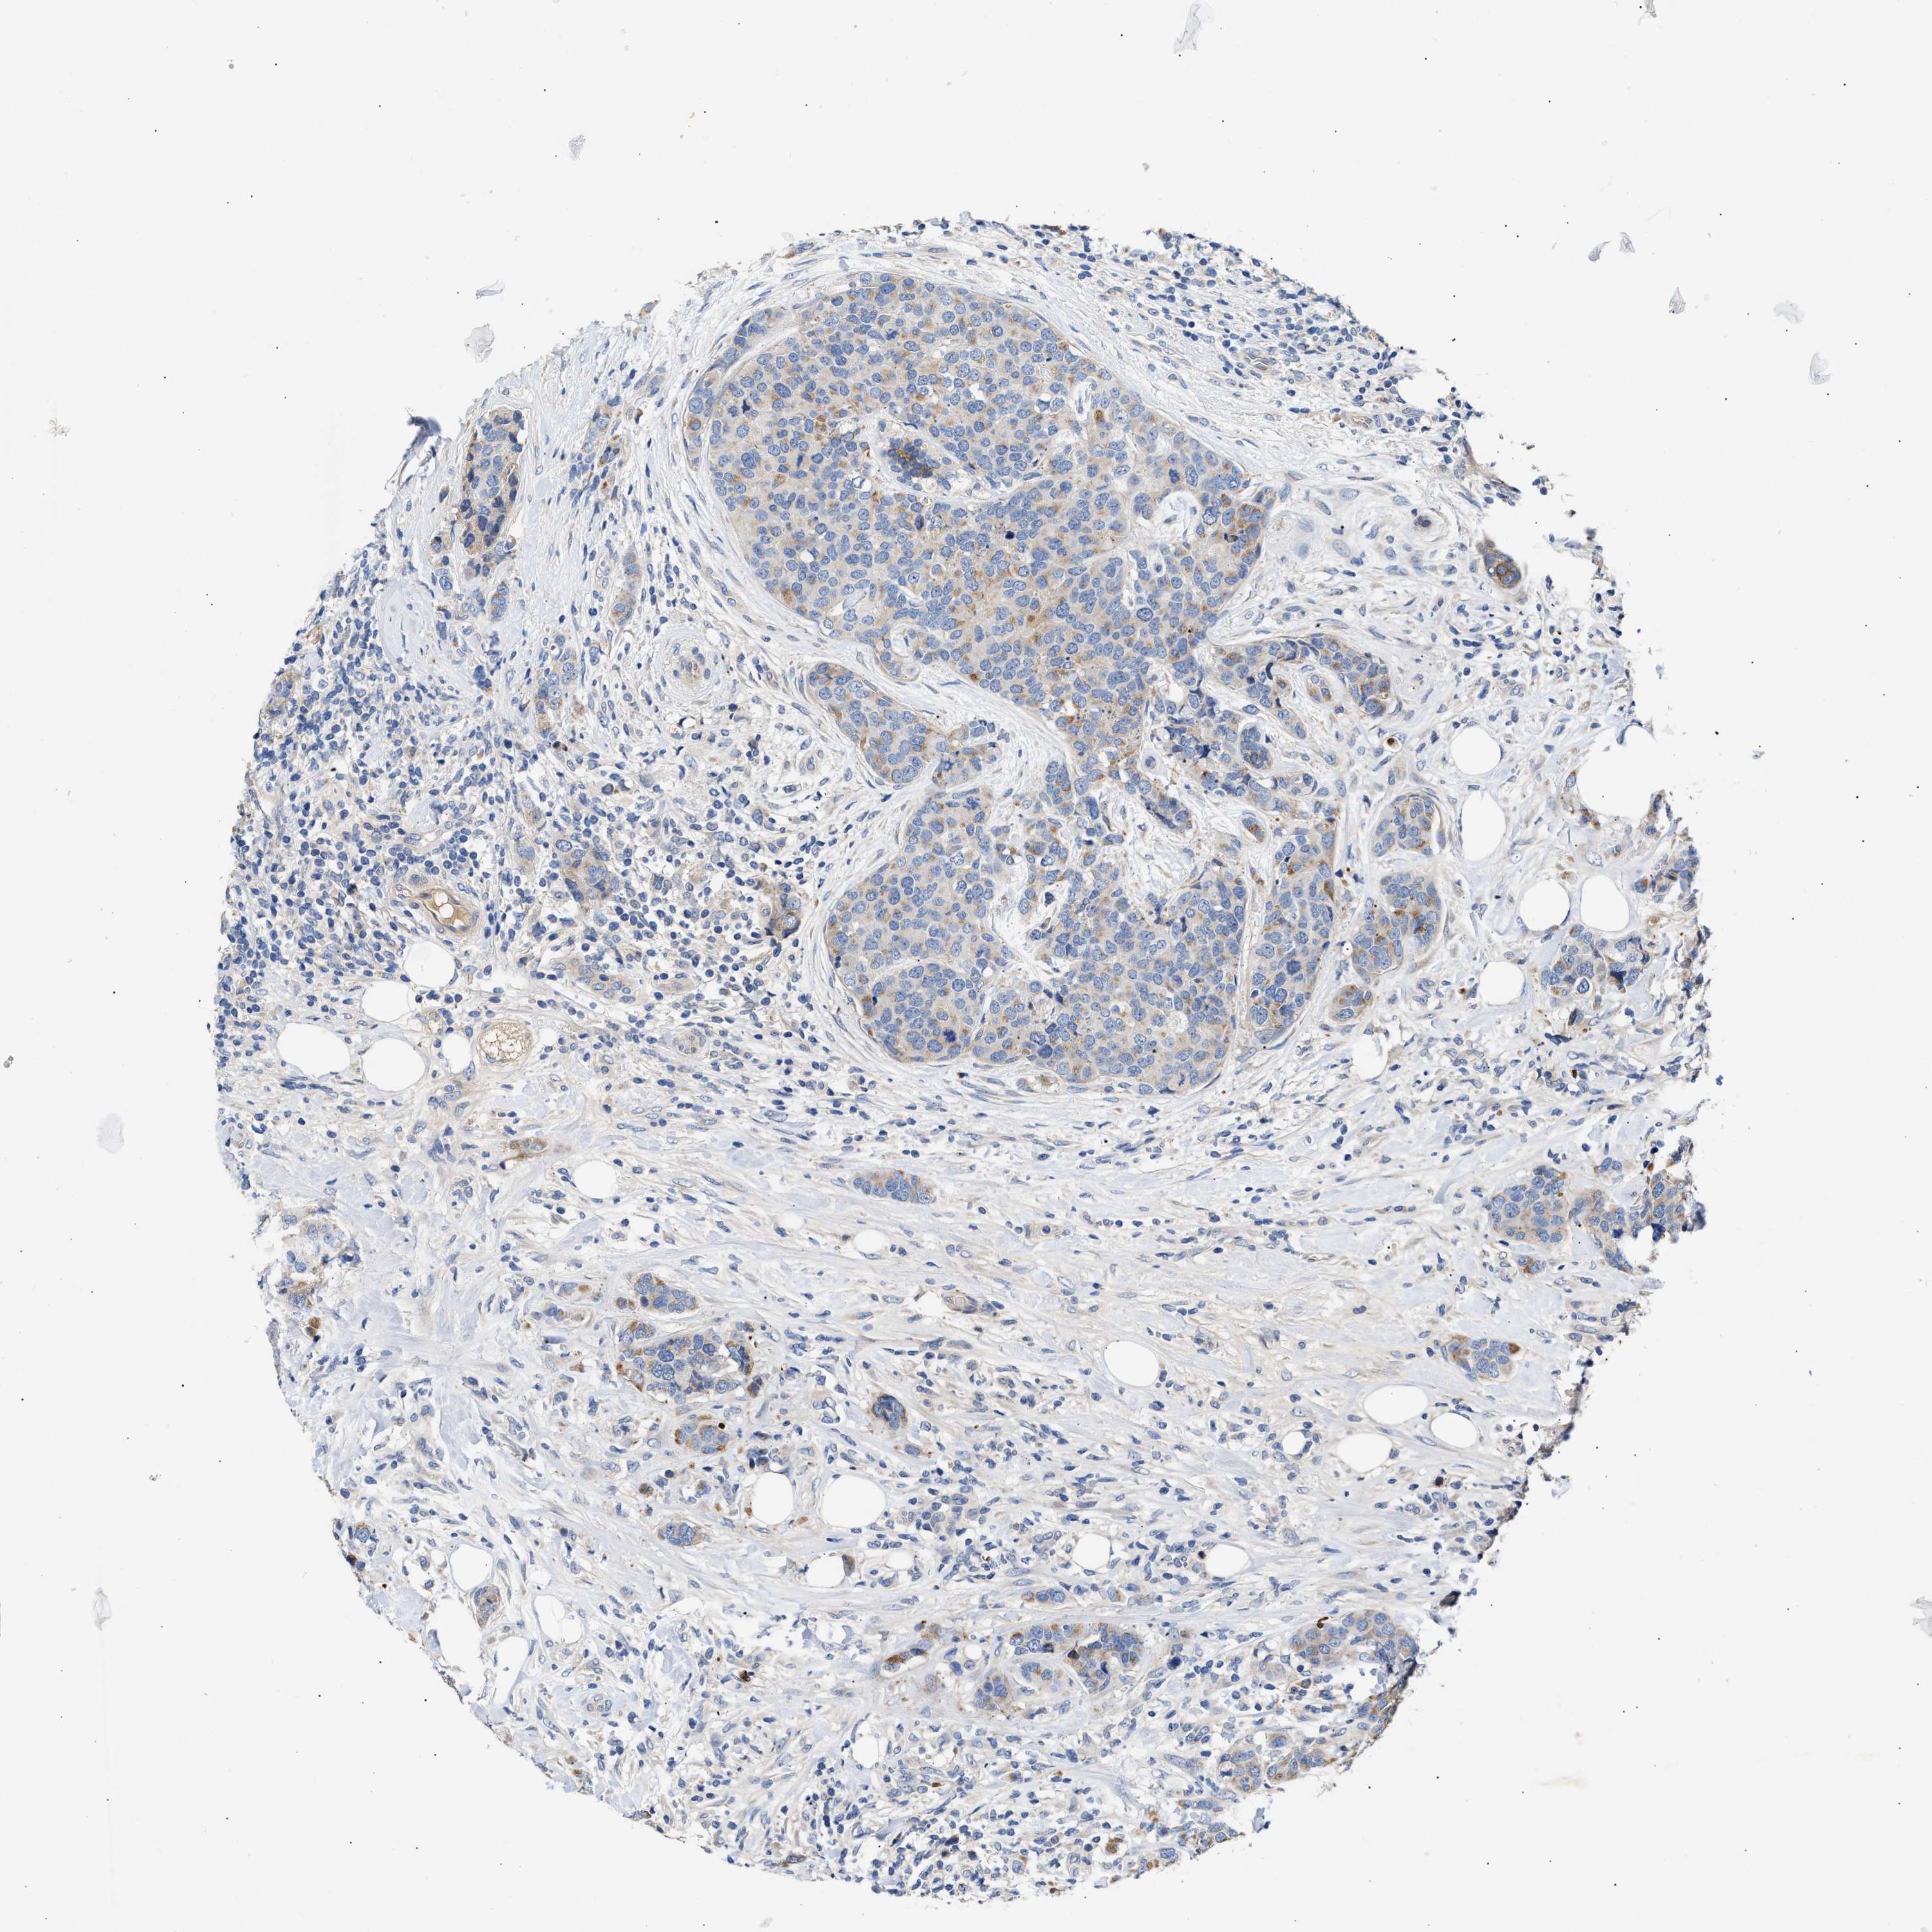

CANCER BREAST CANCER Show tissue menu

BRCA TCGA BRCA VALIDATION PROTEIN EXPRESSION

ANTIBODIES

AND

VALIDATION